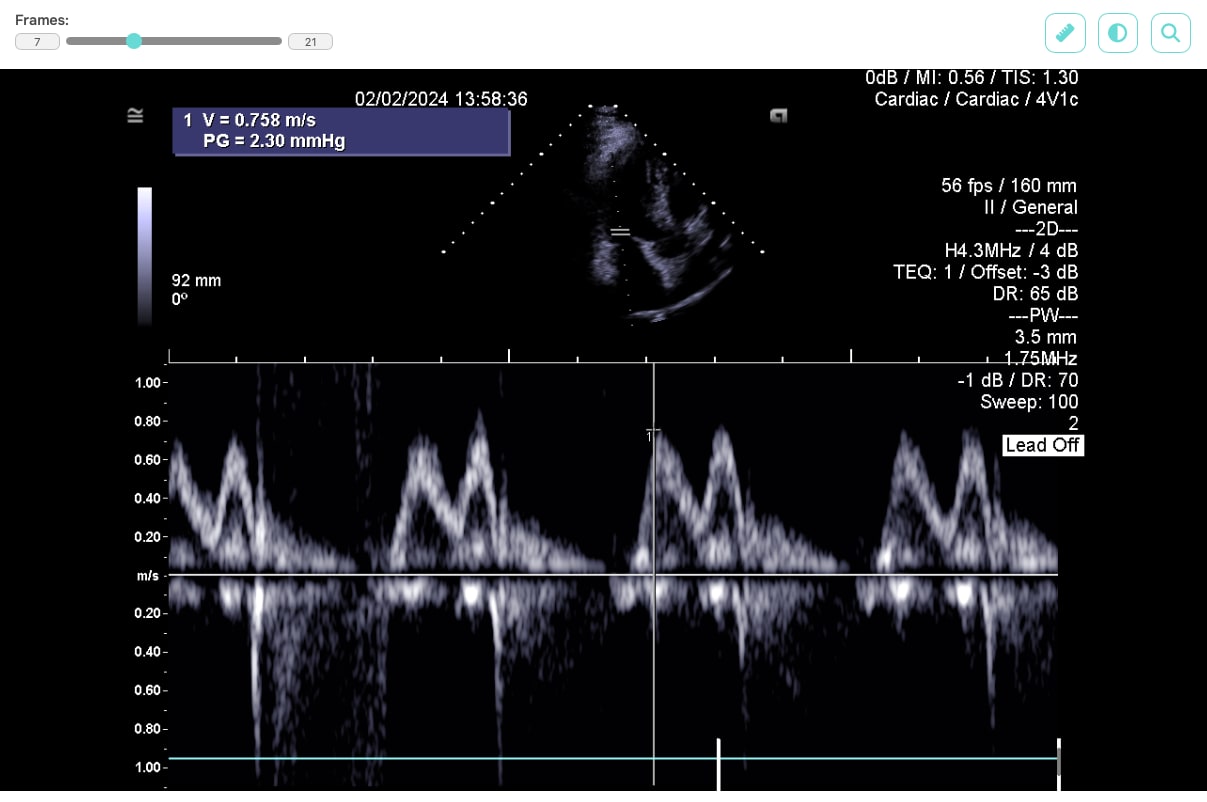

Pro zobrazení dat na webu jsme vybrali JavaScriptovou knihovnu Cornerstone3D, která umožňuje DICOM soubory nejen zobrazovat, ale můžeme u nich například měnit jas, kontrast nebo použít pravítko pro měření vzdáleností mezi zobrazenými částmi pacientova těla.